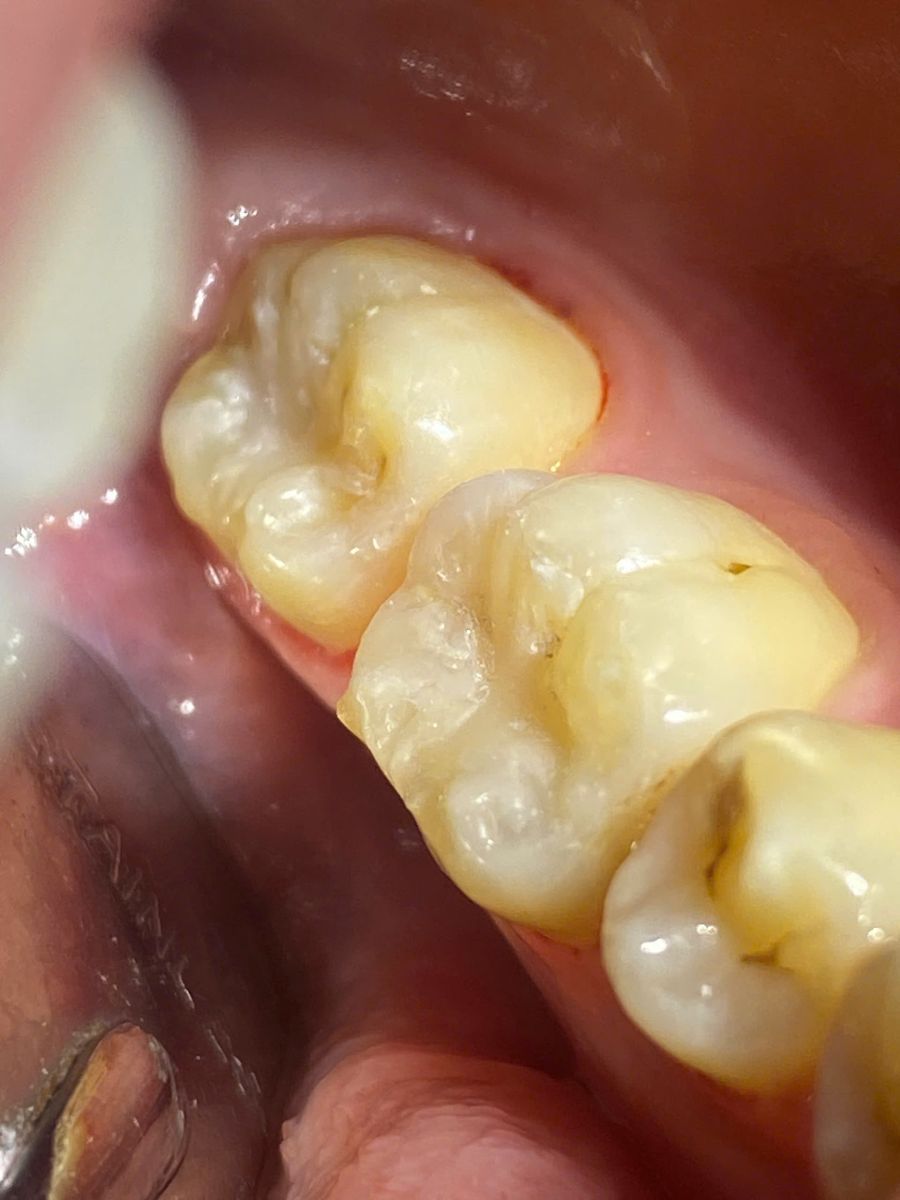

Bước 1: Khám và chẩn đoán

Bác sĩ thăm khám tổng quát, đánh giá mức độ sâu răng. Trường hợp cần thiết sẽ chỉ định chụp phim X-quang để xác định chính xác vùng tổn thương.

Bước 2: Loại bỏ mô răng sâu

Sau khi gây tê cục bộ (nếu cần), bác sĩ sử dụng dụng cụ chuyên dụng để làm sạch hoàn toàn phần mô răng bị sâu.